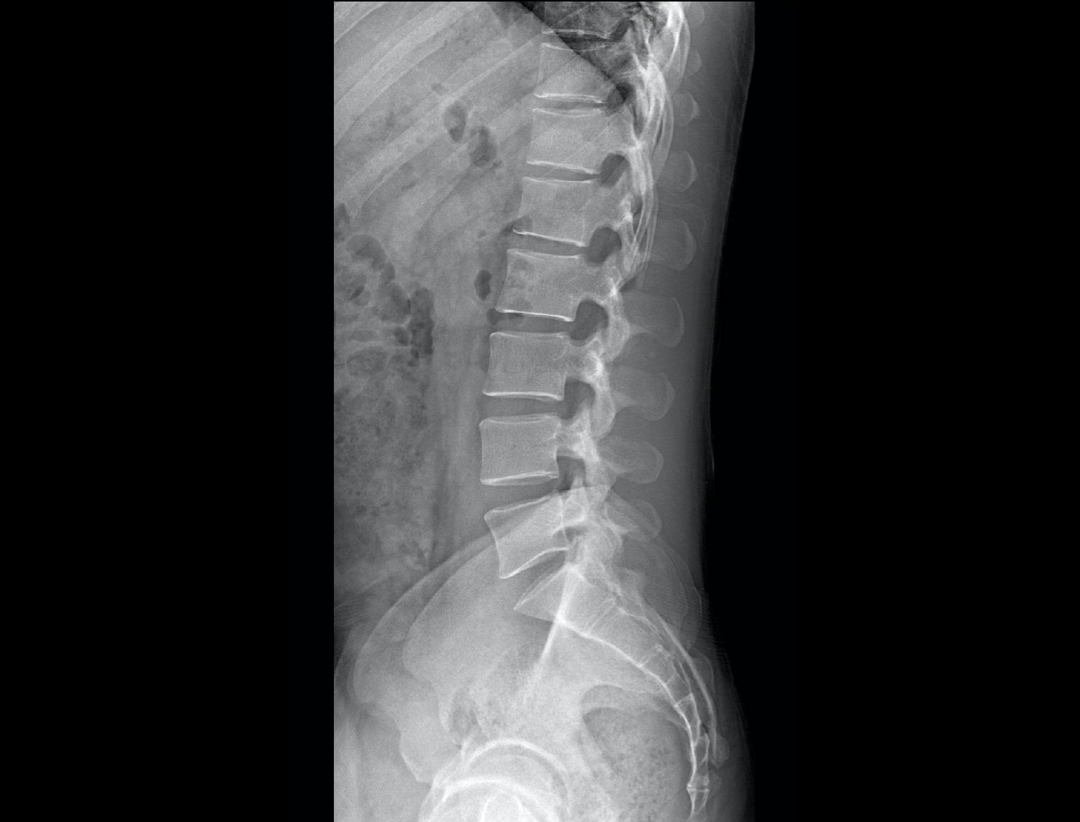

全自动无尺全景拼接

支持自动立位及卧位无尺全景拼接,为骨科、整形外科提供高质量全景影像。

测量功能*

集成脊柱Cobb角及股骨颈干角测量功能,精准指导外科手术及术后评估。

全脊柱正位、侧位